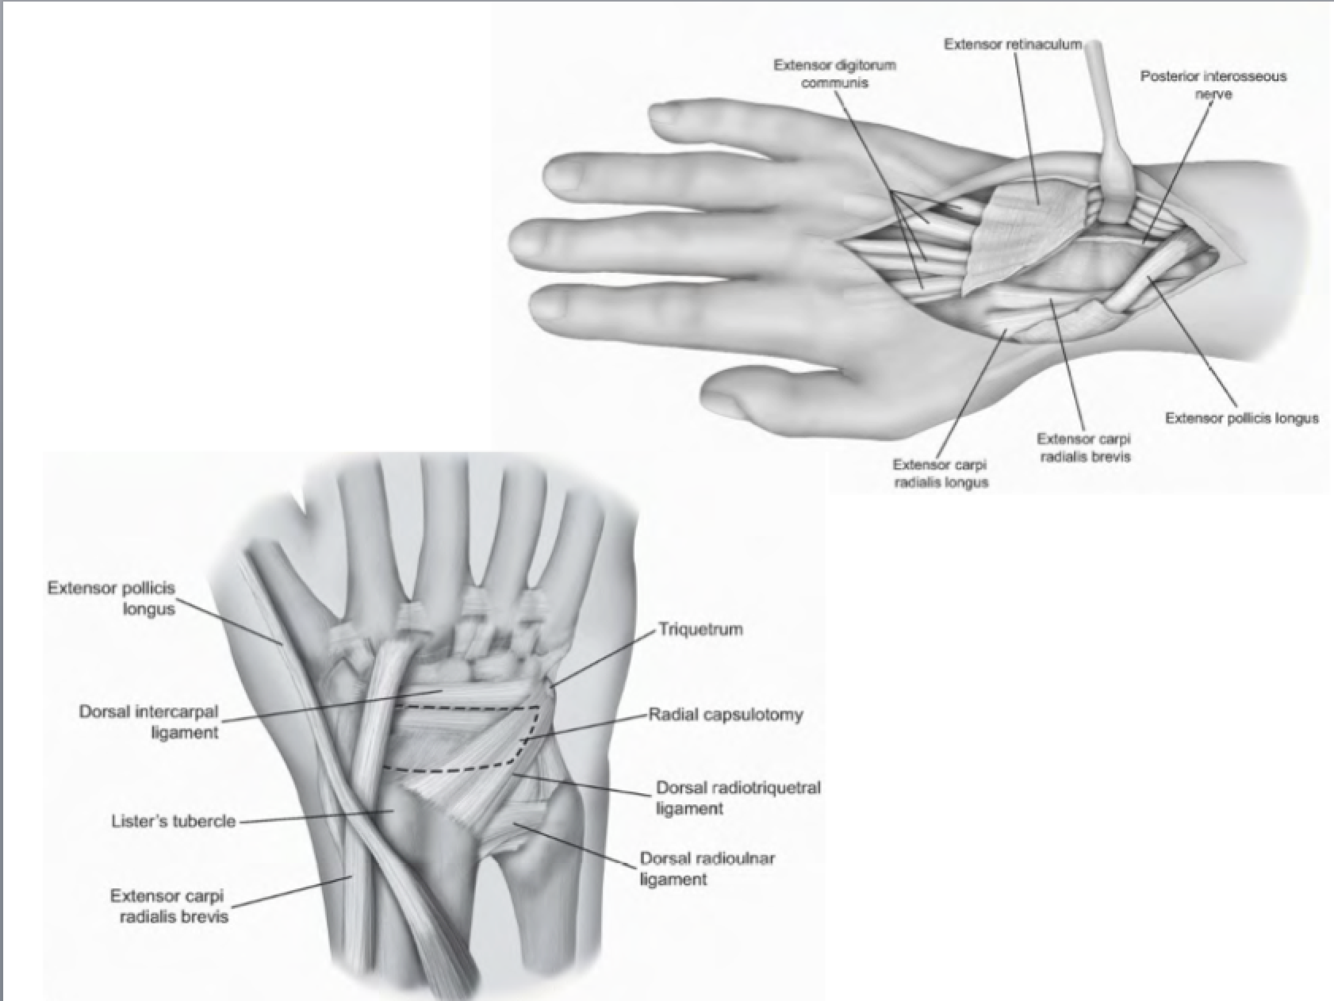

Dorsal Approach to the Wrist

Interval: 3rd & 4th extensor compartments (both PIN).

Approach:

- Incision centered over Lister’s tubercle

- Elevate skin flap, excise extensor retinaculum.

- Identify 3rd and 4th compartment and split the two.

- Identify dorsal wrist capsule, dorsal intercarpal ligament, and dorsal radiocarpal ligament. (Ligament sparing capsulotomy)

Dangers: PIN purely sensory at the wrist (can be ablated for pain control). SL, LT ligaments.